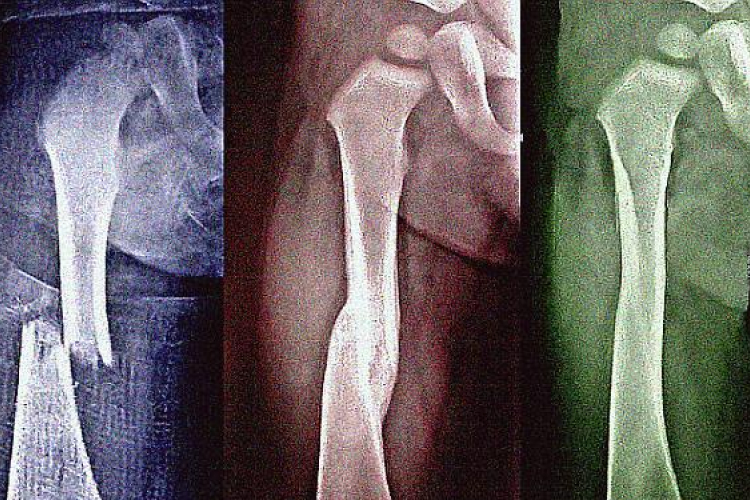

Gyógyuljon gyorsabban a törött csont

Sokan nem tudják, hogy a csonttörés után gyorsítani lehet a gyógyulást. Mindenekelőtt sok energiát vigyen be a szervezetébe, mert a csontok gyógyulásához energia kell.